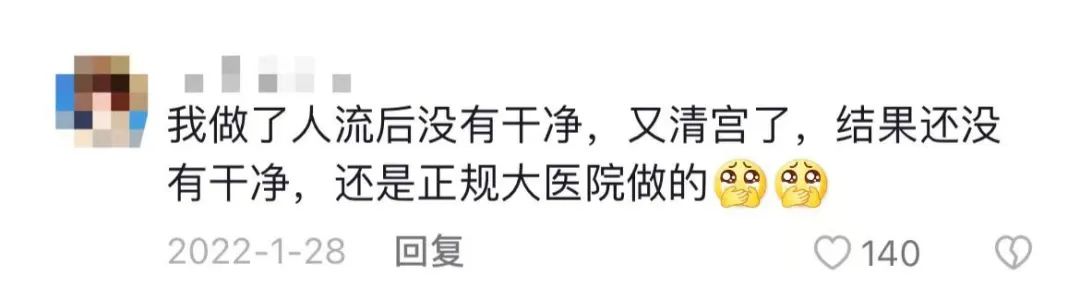

那么,流产的真实感受是什么样的呢?无痛人流,真的能做到不痛吗?

答案显然是否定的。

众所周知,胚胎是由精子与卵子结合形成,之后到子宫壁上着床发育。

所以,流产的过程中,需要用子宫扩张器接连不断地插入孕妇*体下**,用一根粗大的流产吸引管伸进去,像是吸尘器一样,撕碎孩子,把它吸走。

吸走之后,为了确保无胚胎残留,还必须用金属器械把子宫内壁“刮”一遍。